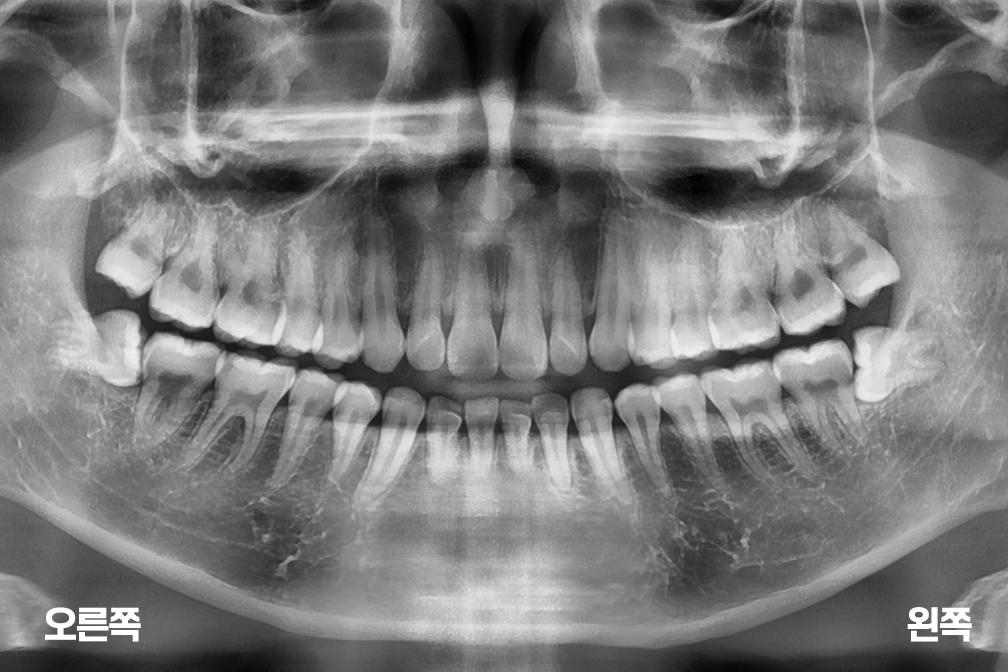

사랑니발치 4개의 사랑니 발치

사랑니 발치